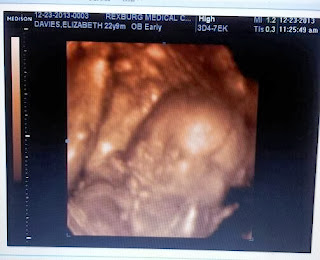

Also, our little Finchbird (we are calling him Finch which is short for his middle name, Finchley, partially after my one of my favorite literary characters, Atticus Finch, and a province in London, my favorite city in the world) is doing so well. He kicks more and more now, and landmark moment: Ben felt him kick a few days ago for the first time! He touched my tummy while we were watching a show on his laptop when I felt Finch kick. I asked Ben if he felt it and he said yeah. I told him that was a kick and he got excited because he thought it was just a hard heartbeat from my abdomen. Nope, it was a kick! We've discovered that Finch is fan of folk music, opera (he really is my son, Luciano Pavoratti has the kick of approval :) ), and I have a new playlist ready so I can introduce him to my favorites while he is in my tummy and can't escape :). When I lay on my left side especially, I can feel him moving, and when I lightly tickle my tummy, he responds. We are pretty much head over heels in love with this baby, we've probably watched our ultrasound 20 times and it's only been a week since we got the disc.